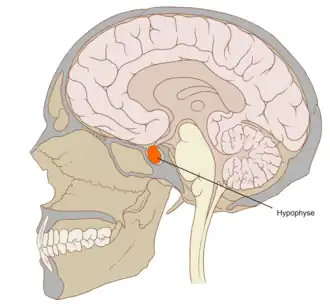

![]() Localización de la hipófisis (color rojo) en la base del cráneo. | ||